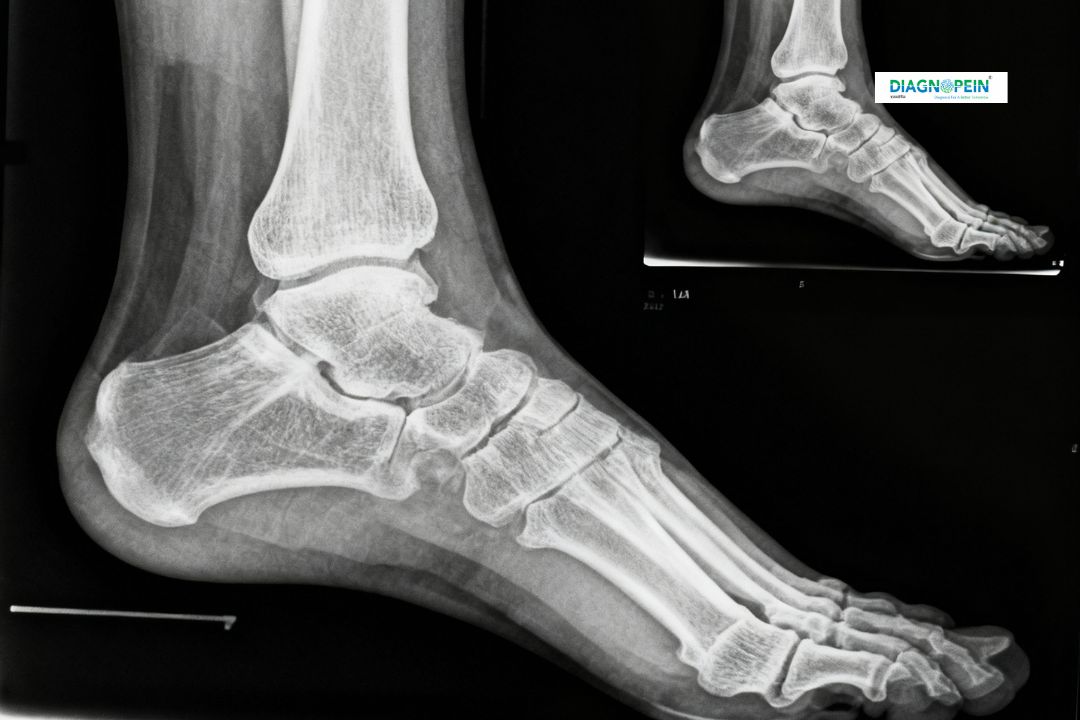

X-Ray Right Ankle AP/LAT is a diagnostic imaging test used to examine the ankle joint bones, ligaments, and surrounding tissues. The term “AP/LAT” refers to two standard views – Anteroposterior (front to back) and Lateral (side view) – that help radiologists capture a complete structural overview of the ankle joint.

Performing an X-Ray of the right ankle in both AP and Lateral views is essential because a single angle cannot reveal all bone and joint structures precisely. This imaging provides:

1. A clear view of the tibia, fibula, and talus alignment.

2. Detection of small or complex fractures.

3. Insight into degenerative diseases like osteoarthritis.

4. Assessment of post-surgical healing after bone repair.

1. Bone alignment evaluation (tibia, fibula, talus)

2. Joint space integrity

3. Signs of bone fractures or deformities

4. Soft tissue swelling or foreign objects

5. Post-operative healing status